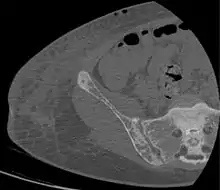

CT shows focal areas of osteosclerosis.[18]